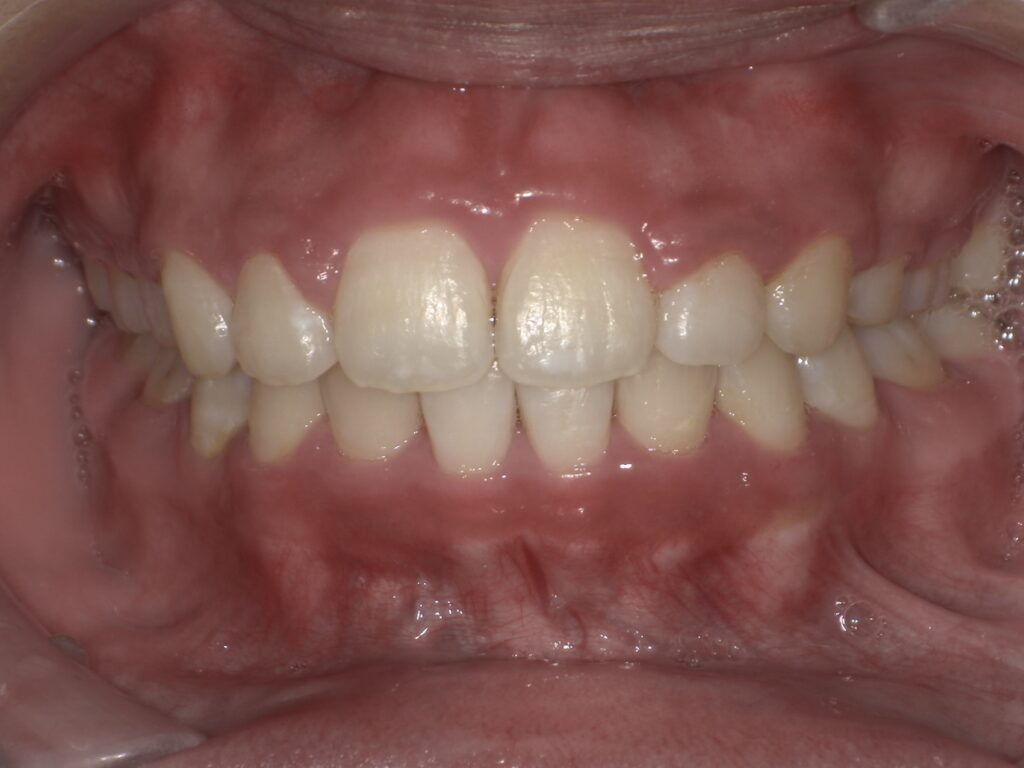

【マウスピース矯正】

矯正前(正面・側貌)

矯正後(正面・側貌)

主訴すきっ歯

初診年齢38歳

治療内容、装置アライナー

抜歯、非抜歯非抜歯

治療期間8ヶ月

費用473,000円

(相談料、検査料、診断料、動的治療費、保定期間料を含む)

治療のリスク、副作用歯の移動に伴う痛み

上下顎前歯部の歯根吸収

ブラッシング不良によるむし歯、歯周炎